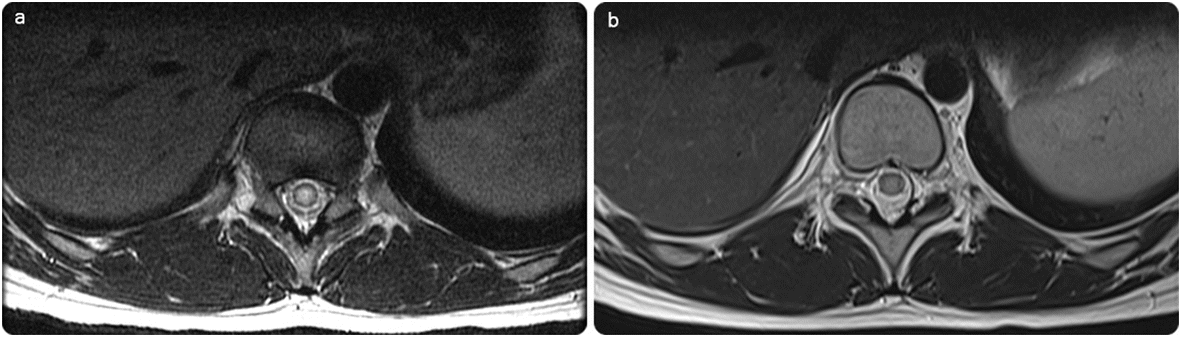

a Initial axial T2 of the dorsolumbar spine shows intramedullary expansion with T2 hyperintensity. b Significant regression in the follow-up image post-praziquantel treatment, with normalizing signal of the spinal cord